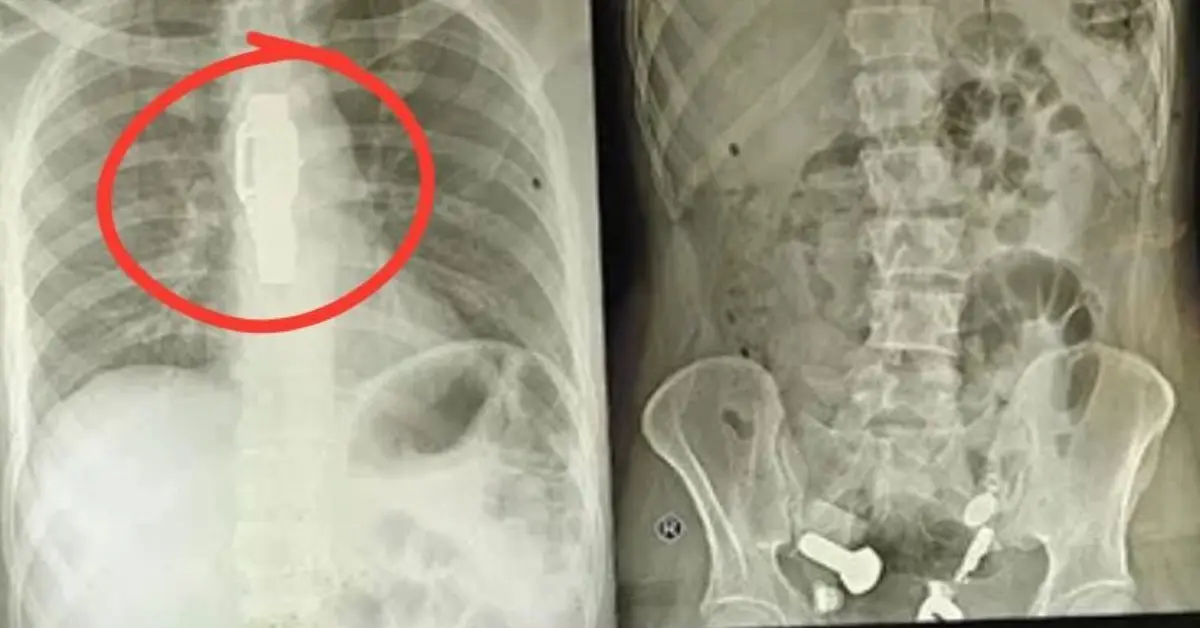

直到安排了影像學檢查,全體醫護人員才被螢幕上的畫面驚得說不出話:男子的食道中段卡著一整只手錶,而腸道裡更是像被刻意塞滿了「五金配件」,鐵片、螺絲、螺帽與大理石塊隨處可見,簡直是個移動的小型雜物堆。

印度齋浦爾一名34歲男子因劇烈腹痛嘔吐就醫,竟發現食道卡著整只手錶,腸道堆滿鐵片等硬物。醫護團隊歷3小時手術取出異物,研判其行為與精神疾病引發的幻覺及衝動有關,術後心理治療至關重要。(來源:網絡)